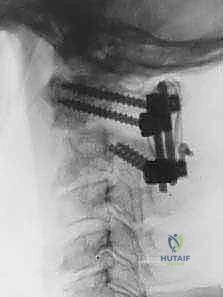

تُعرف التقنية الأكثر شيوعاً وفعالية اليوم باسم تقنية هارمز/جويل (Harms/Goel Technique)، والتي تتضمن وضع مسامير في الكتل المفصلية للفقرة C1 ومسامير في عنيقة أو جزء (Pars) الفقرة C2، ثم ربطها بقضبان معدنية. يتطلب هذا الإجراء مهارة جراحية فائقة، استخدام الميكروسكوب الجراحي، والتوجيه بالأشعة السينية داخل غرفة العمليات.

يتم تحديد نقطة الدخول على الكتلة المفصلية للفقرة C1. باستخدام مثقاب عالي السرعة (High-speed burr) ثم مثقاب يدوي دقيق، يتم عمل مسار للمسمار. يتم توجيه المسار بدقة ليكون موازياً للقوس الأمامي ومتجهاً قليلاً للداخل نحو مركز الفقرة لتجنب الشريان الفقري الذي يقع في الخارج. يتم إدخال مسمار من التيتانيوم (عادة بقطر 3.5 مم) في كل جانب.

الخطوة 5: إدخال المسامير في الفقرة الثانية (C2 Pedicle/Pars Screws)

الخطوة 6: تركيب القضبان واستعادة المحاذاة (Reduction)

بعد وضع المسامير الأربعة بنجاح، يتم تقييم وضعية الفقرات. إذا كانت C1 منزلقة للأمام، يتم استخدام أدوات خاصة لسحبها للخلف واستعادة المحاذاة الطبيعية مع C2 (عملية تُسمى Reduction). بمجرد تحقيق الوضعية المثالية، يتم قص قضيبين من التيتانيوم بالطول المناسب وتثبيتهما بقوة في رؤوس المسامير. هذا يخلق "سقالة" معدنية صلبة تمنع أي حركة بين الفقرتين.